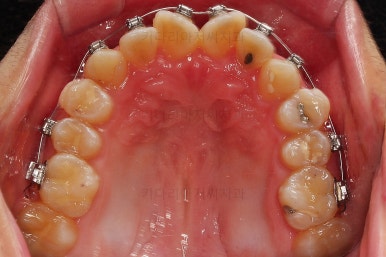

먼저 장치를 부착하고요.

환자분이 선택하신 장치는 자가결찰 메탈장치 입니다.

메탈이라고 모두 구시대적 장치는 아니에요. 자가결찰인지 아닌지가 구세대나 아니냐를 결정하는 기준이에요.

즉, 예를들면 자가결찰 메탈은 요즘세대, 그냥 세라믹은 구세대라 할 수 있어요.

자가결찰 중에서도 메탈도 있고 세라믹도 있는거고, 자가결찰 세라믹 중 클리피씨, 데이몬 클리어, 엠파워 클리어 등이 있습니다.

메탈은 강도가 높고, 부피도 작고, 위생관리에 약간의 장점이 더 있어요.

대신 보이는 측면에서의 단점이 있기 때문에 장단점을 고려해서 입맛에 맞게 선택하시라고 말씀 드리는 편이에요.